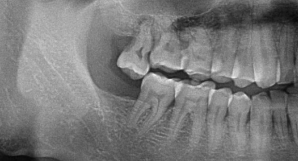

②生长位置不正智齿长歪挤压邻牙或出现阻生智齿。

智齿长歪和相邻的恒牙挤着生长,会不易清洁,当生长空间不足时,还会出现严重的牙龈肿胀,甚至导致前牙歪斜、排列拥挤,牙列不齐阻生智齿(智齿刺客)通常都埋在牙槽骨里面,非常容易被忽略,需要通过拍牙片诊断。